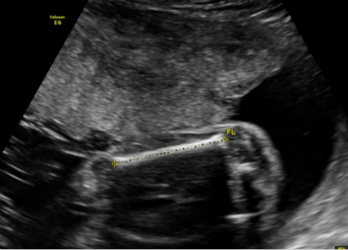

3.妊娠28周~32周超声检查;主要进行胎儿生长发育情况的评估、测量及部分胎儿结构畸形的筛查。

2.妊娠18周~24周超声检查:主要进行胎儿结构畸形的系统筛查。此时期胎儿各器官已发育成熟,系统产前超声检查可记录胎儿各器官结构包括头颅、面部、胸腹腔、心脏、肝脏、双肾、肢体及胎盘等结构,可发现大多数胎儿结构畸形。此阶段是观察胎儿结构和诊断胎儿畸形黄金时段,我们建议所有孕妇在此阶段务必接受一次超声检查。

3.妊娠28周~32周超声检查:对一些在胎儿发育过程中才逐渐表现出来的胎儿畸形进一步筛查,以及对之前检查可能漏诊的畸形补漏。同时,观察这个时期胎儿的生长发育情况,监测有否胎儿宫内生长迟缓。